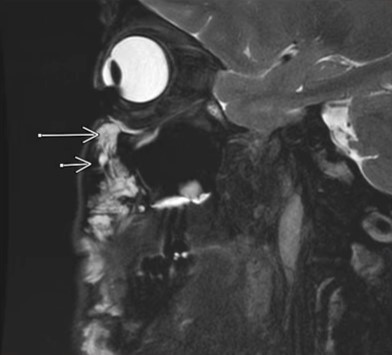

以下这张就是一个在嘴唇打过玻尿酸的患者的扫描图:

箭头指向的白 {MOD}部分就是残余的玻尿酸,上唇和下唇都有,甚至的上唇上面有一圈看起来像“长胡子”。

就以玻尿酸丰唇为例,很多人每隔一段时间就会去注射玻尿酸,因为他们觉得每次打完能维持的时间太短了。但是从MRI仪器里面看的话,会发现皮肤里的玻尿酸其实在越来越往上移动,越来越靠近鼻子,而不是消失了。